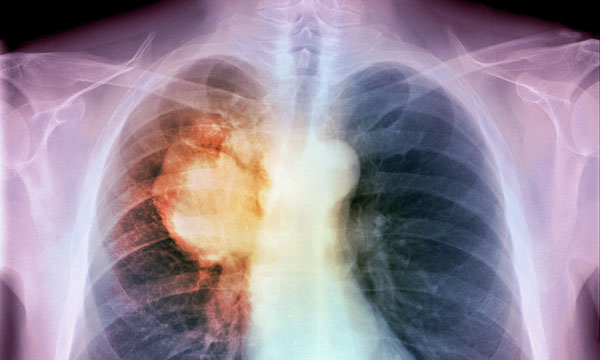

More late-stage lung cancer diagnoses among 50-64s than in 65-69 age group